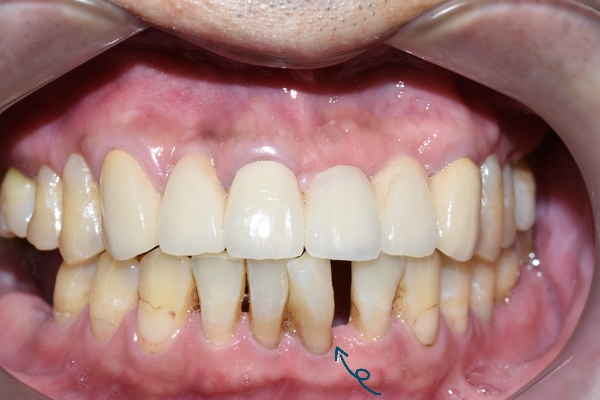

환자분은 40대 남자분으로, 아래 앞니가 원래 안이랬는데 점점 벌어진다고 하셨습니다.

이렇게 앞니가 벌어지게 되면 입안 틈이 까맣게 보여서 미관상 좋지 않은 것이 사실입니다.

환자분의 앞니 교정전 치아 상태입니다.

[2019년10월의 사진입니다.]

어떤 치아가 문제인지 한눈에 보입니다.

치아가 틀어진 정도가 심해서 이런 치아는 일반 앞니 부분교정 보다

좀 더 심화적인 조치를 취해야 했습니다.

보통 앞니 부분교정은 3~5개월 정도로 완료되고

이분의 경우는 틀어진 정도가 심해서 처음 배열전 추가적인 조치를 하느라

6개월만에 완료되었습니다.

사회생활을 하는 40대 남자분이지만, 보이지 않게 안쪽으로 붙이는 설측앞니교정을 하여

남들 모르게 교정을 마무리할 수 있었습니다.